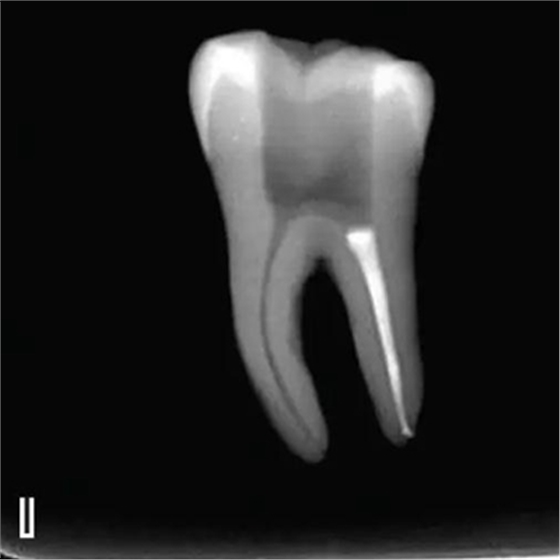

8、熱牙膠根中上段的充填

在完成根尖段的充填后,使用熱塑牙膠注射儀對(duì)根管中上段進(jìn)行分層充填,一般分2~3次完成充填,每次充填均使用相應(yīng)直徑大小的垂直加壓器進(jìn)行加壓。拍片確認(rèn)充填效果(圖8)。

圖8 熱牙膠根中上段的充填,A、B.注射儀注射中段熱牙膠

C、D.垂直加壓器加壓 E、F.注射儀繼續(xù)注射上段熱牙膠

G、H.垂直加壓器加壓 I、J.完成根中上段的充填